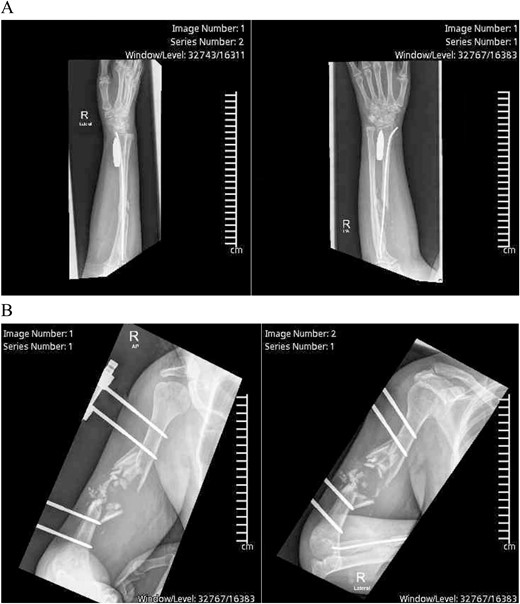

Right upper limb X-rays revealed external fixation device with pins at the proximal and distal ends of the right humerus with shattered mid-third of the shaft, surrounded by displaced fracture fragments, crushed proximal radius fracture with intramedullary nailing noted in satisfactory position, and a 5 × 1 cm bullet was seen lying longitudinally along the volar aspect of the distal radius (Fig. 1A and B). The carpal bones alignment was maintained A plain CT scan of the upper limb showed the comminuted fracture of the right humerus with multiple bone fragments and displacement.

(A) Preoperative X-ray showing the bullet lodgment along the volar aspect of the distal radius. (B) Preoperative X-ray showing the external fixation device with pins at the proximal and distal ends of the right humerus with shattered mid-third of the shaft, surrounded by displaced fracture fragments, which was shattered along the bullet’s tract before settling in the wrist.